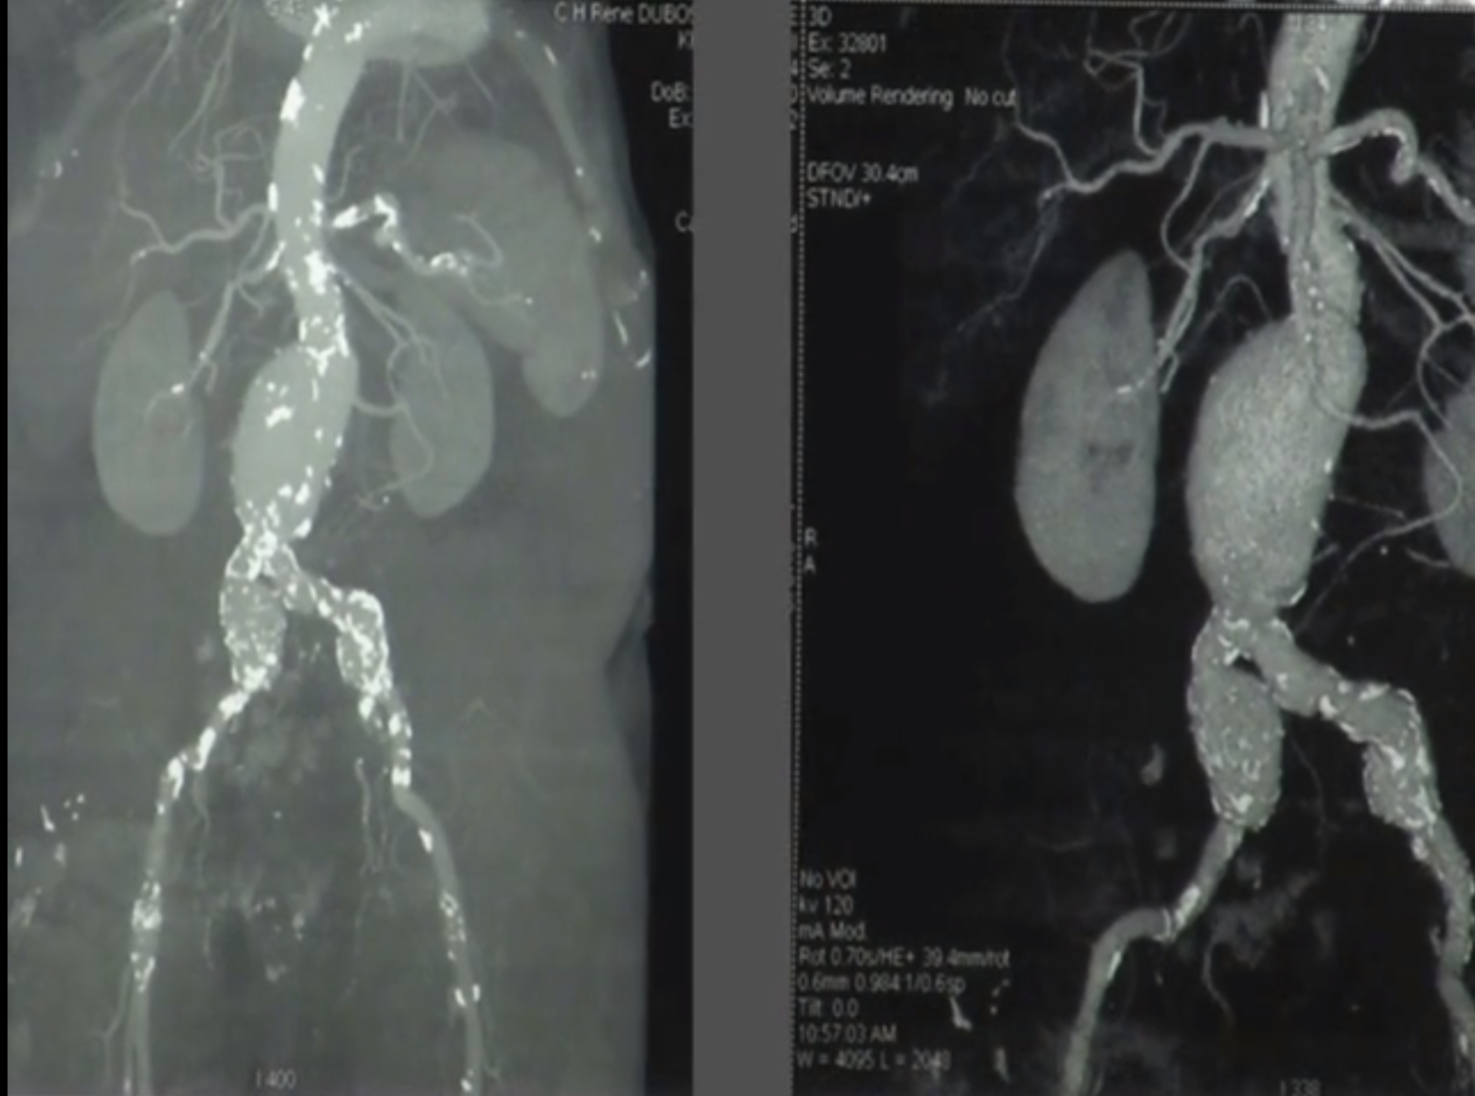

La grande majorité (85%) des anévrismes de l’aorte abdominale est située sous les artères rénales et les artères iliaques sont souvent aussi anévrismales. Si l’anévrisme englobe l’origine des artères rénales, on parle alors d’anévrisme pararénal.

L’angioscanner aorto-iliaque est plus invasif mais plus reproductible que l’échographie et moins opérateur dépendant. C’est l’examen de choix avant un traitement par endoprothèse ou par chirurgie classique. Il permet les mesures exactes (« sizing ») de l’anatomie de l’anévrysme, de l’aorte et des artères iliaques avant mise en place d’une endoprothèse. Il permet la recherche d’autres anévrysmes au niveau fémoro-poplités et d’étudier l’ensemble de l’aorte.